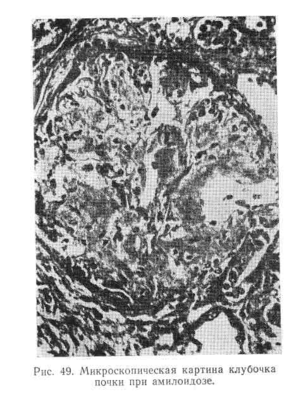

Гистохимические и электронно-микроскопические исследования ткани почек, полученной при помощи пункционной биопсии, показали, что в относительно ранней стадии амилоидной дистрофии поражаются не все петли клубочка. Стенки пораженных петель неравномерно утолщены. В более поздней стадии амилоидная субстанция наводняет весь клубочек, закрывая просвет капилляров, откладывается в стенке артериол, вокруг них, а также в базальной мембране канальцев и в интерстициальной ткани. Нефроны запустевают и атрофируются, в мозговом и корковом веществе разрастается интерстициальная ткань (рис. 49),